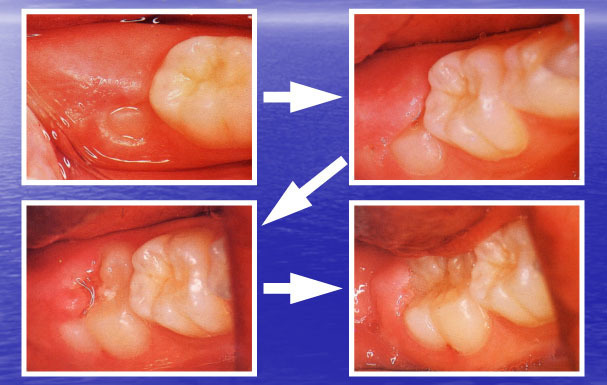

生えかけの期間が長い

完全に生えきるまでに時間がかかり、歯ぐきがかぶった状態で汚れがたまりやすいです。

六歳臼歯が生えかけで歯ぐきに覆われ磨きにくい状態を示した写真